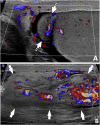

The differential diagnosis of scrotal pain and swelling in adolescent males includes testicular and appendage torsion, epididymitis, epididymo-orchitis, trauma and incarcerated hernia. Physical examination, ultrasound and urinalysis often can identify the etiology of the scrotal pain and swelling. We present a case of left scrotal pain and swelling that was initially concerning for a paratesticular mass. Repeat examination and further imaging during pre-operative assessment was consistent with left-sided vasitis. The diagnosis of vasitis is difficult with ultrasound and commonly requires CT or MRI to differentiate from incarcerated inguinal hernia. Recognition of this uncommonly reported condition may prevent unnecessary surgeries.